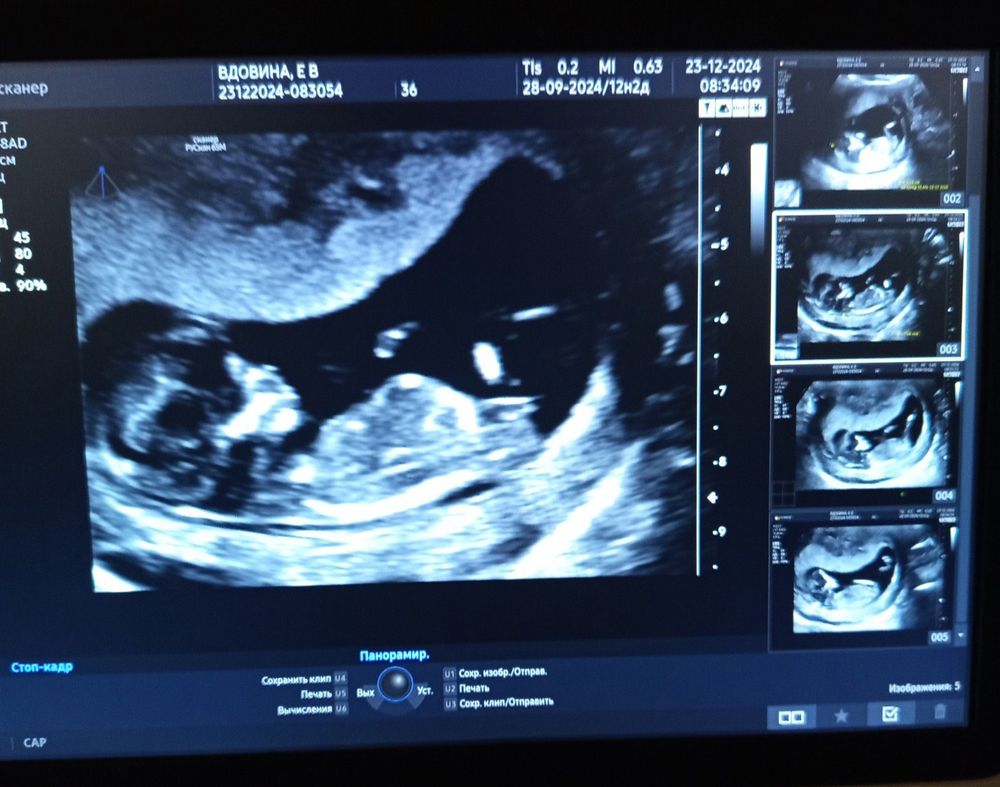

мне не мерили в 9 недель и в 12.Но судя по фото, место есть Изображение

28.12.2024

Изображение